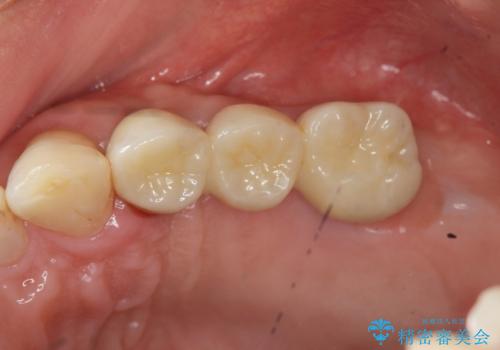

しっかりと造骨を行ったことでインプラント周囲には十分な量の骨が存在し安定したインプラント周囲環境を整えることができました。

最終的なジルコニアクラウン装着後は、まるで自分の歯のように咬める、と咬合機能の回復を大変喜んでいただくことができました。